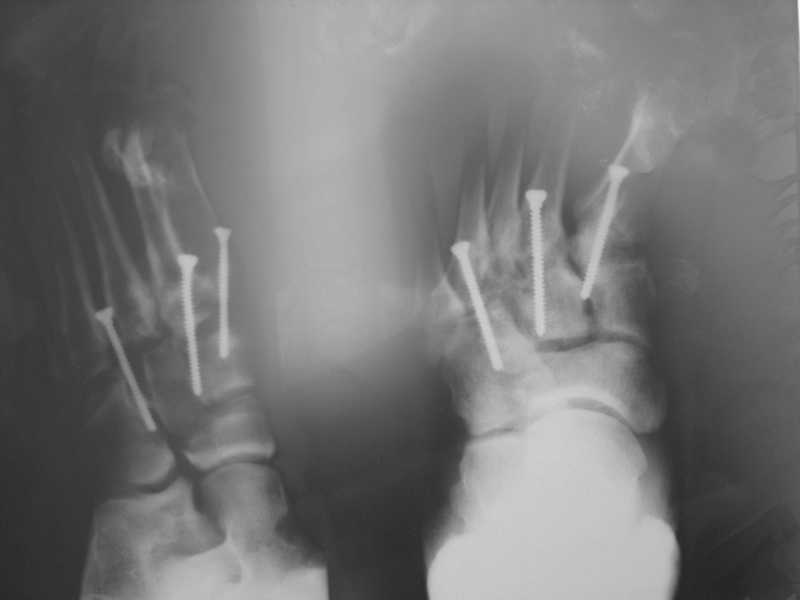

1.на снимке №3 (стопа в боковой проекции с винтами) складывается впечатление о сохраняющемся подошвенном подвивихе в суставе Лисфранака или это искажение при обработке фото?

Вправление и фиксация лисфранка было там же, на оригинальных снимках подвывиха нет.

2. О суставе Лисфранка...

По суставу Лисфранка : 1- 8 -9 нед . полный покой в гипсовой шине,а

потом дозированная нагрузка. 2- Сейчас (на 7 нед.) пригипсовать

каблук под пятку и давать дозированную нагрузку, и на 12 нед,

Собственно такая фиксация сустава после вывизи никакой гипсовой иммбилизации не подразумевает! Через 6 недель винты можно удалять и разрешать полную нагрузку.... Прошло уже 7 недель, на сколько я понял, .....

Резюме: Удаляйте сейчас винты из стопы, динамизируйте стержень на бедре..Дайте нагрузку... Обсудите с больным вероятность и необходимость возможной реоперации на бедре, не дожидаясь таких осложнений как несращение, рефрактура и/или перелом штифта...